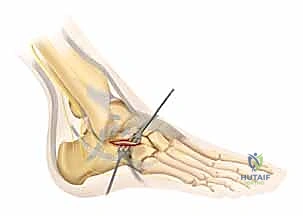

1. وضعية المريض والشق الجراحي

يتم وضع المريض على جانبه السليم. يقوم الدكتور هطيف بعمل شق جراحي دقيق على شكل حرف "L" على الجانب الخارجي للكاحل. يتم تصميم هذا الشق بعناية فائقة للحفاظ على التروية الدموية للجلد وتجنب إصابة العصب الربلي (Sural Nerve).

خطوة بخطوة: كيف يجري الدكتور محمد هطيف العملية الجراحية؟

تتم الجراحة تحت التخدير النصفي أو العام، وتستغرق عادة من ساعتين إلى ثلاث ساعات، وتتضمن الخطوات الدقيقة التالية:

صور إضافية من داخل غرفة العمليات توضح دقة الإجراء

توضح الصور التالية مدى تعقيد الجراحة والدقة التي يتطلبها تثبيت عظم الكعب، والتي يعكسها التميز الجراحي للأستاذ الدكتور محمد هطيف: